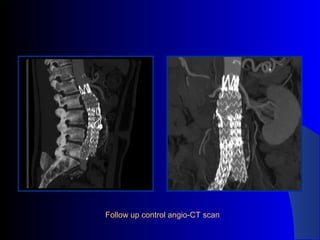

The document discusses the clinical application of the Endurant stent graft system in treating aorto-bisiliac aneurysms, detailing procedures performed on two male patients aged 72 and 73. Each patient had a history of dyslipidemia and carotid atherosclerosis, with procedures involving the bilateral bell bottom technique and the use of coils and fibrin glue. It includes pre-surgery imaging, intrasurgery angiography, and follow-up control scans to monitor outcomes.